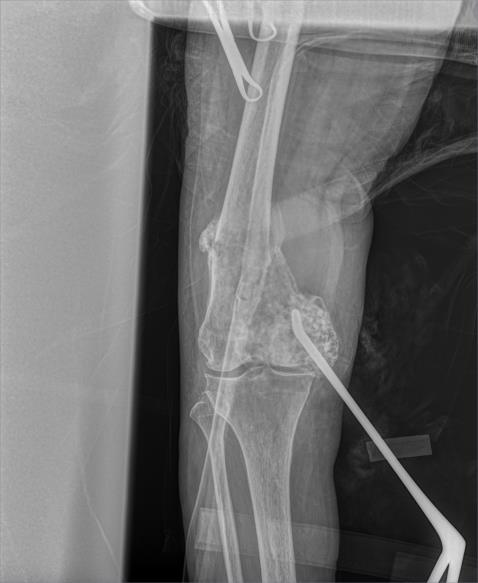

Mujer de 49 años. Dolor en pierna  de 2 años de evolución.

Dolor en pierna  de 2 años de evolución

Incremento de dolor

Fractura de fémur

Condrosarcoma desdiferenciado